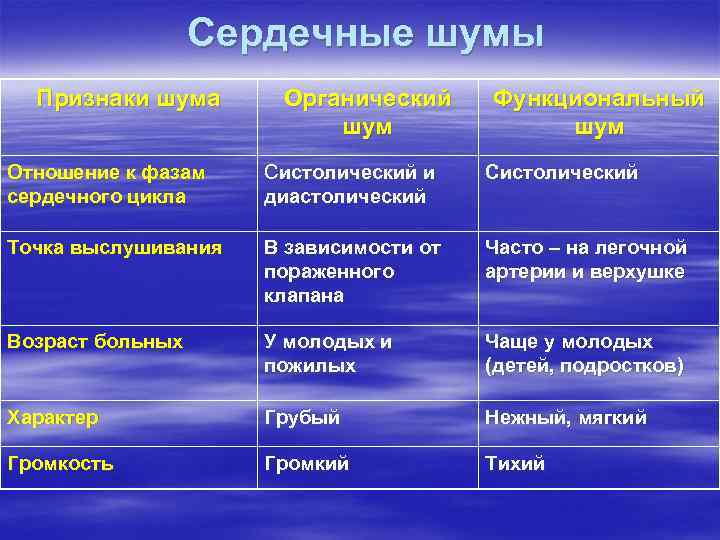

Сердечные шумы Признаки шума Органический шум Функциональный шум Отношение к фазам сердечного цикла Систолический и диастолический Систолический Точка выслушивания В зависимости от пораженного клапана Часто – на легочной артерии и верхушке Возраст больных У молодых и пожилых Чаще у молодых (детей, подростков) Характер Грубый Нежный, мягкий Громкость Громкий Тихий

Сердечные шумы Признаки шума Органический шум Функциональный шум Отношение к фазам сердечного цикла Систолический и диастолический Систолический Точка выслушивания В зависимости от пораженного клапана Часто – на легочной артерии и верхушке Возраст больных У молодых и пожилых Чаще у молодых (детей, подростков) Характер Грубый Нежный, мягкий Громкость Громкий Тихий